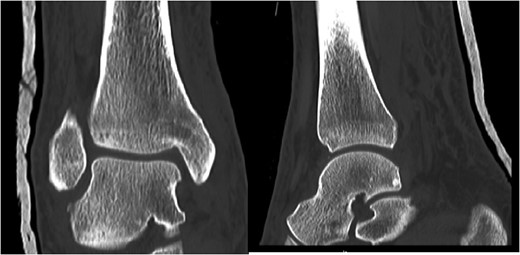

A 30-year-old male patient presented to Emergency Department (ED) following a run over injury. The patient described the mechanism of injury as moving his body over his run over foot. On clinical examination, there was obvious deformity and swelling of the right ankle. Dorsalis pedis pulse was felt but weak compared to the contralateral side with a capillary refill time under 3 s. The posterior tibial artery could not be palpated because of the deformity. X-rays showed posterior ankle dislocation without associated fractures (Fig. 1). Urgent reduction of the dislocation was done under sedation in ED. The knee was first flexed to relax the tendon Achilles then longitudinal traction with gentle forward force applied to the heel with immediate reduction of the deformity achieved. The foot was reassessed for vascular status. Triphasic pulse in both drosalis pedis and posterior tibial artery was detected with hand held Doppler. Ankle was immobilized in posterior below knee back slab to accommodate for swelling and check x-rays confirmed reduction of the ankle joint (Fig. 2). CT scan was done afterwards to define any subtle incongruity or osteochondral fragments entrapped in the joint. CT did not show any associated fractures and showed congruent reduction of the ankle joint (Fig. 3). Patient was mobilized touch weight bearing for first 2 weeks. The back slab was changed for weight bearing short leg cast and progressive weight bearing was allowed for the following 4 weeks. At 6 weeks follow up, plaster was removed and on examination patient still had moderate tenderness over the medial joint line and deltoid ligament area. Also, patient had limited range of plantar and dorsal flexion. Referral for physiotherapy was done for start of functional rehabilitation and range of motion exercises and in mean time MRI was done to delineate extent of ligamentous injury. MRI showed bone bruising of the lateral malleolus, medial malleolus and lateral talus (Fig. 4). The anterior talufibular ligament (ATFL), calcaneofibular ligament (CFL), posterior talofibular ligament (PTFL) and deltoid ligaments were sprained but intact. At 12 weeks follow up, patient could walk normally without any symptoms of instability and achieved 20° of both plantar and dorsal flexion. At 16 weeks, patient achieved full range of motion of ankle and was able to return to work. At 24 weeks follow up patient was able to resume his sport activates as preinjury level.

T2 MRI images showing high signal in medial malleolus, lateral malleolus and talus signifying bone bruise.